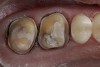

Figure 3  Gingival tissues have been retracted with cord in readiness for the digital impression.

Figure 3

A patient presented with large amalgam restorations and recurrent caries on teeth Nos. 2 and 3 (Figure 2). After reviewing the treatment options, the patient chose all-ceramic crowns to restore the teeth. The specific all-ceramic crowns selected for the case were zirconia crowns. After completion of the crown preparations, soft-tissue retraction was achieved and the tooth surfaces were cleaned and dried (Figure 3). The teeth and soft tissues were isolated and lightly sprayed with a titanium-dioxide powder to create a reflective surface (Figure 4). The powder provides contrast points for scanning to enhance recording the 3-D models and to improve the speed of recording.